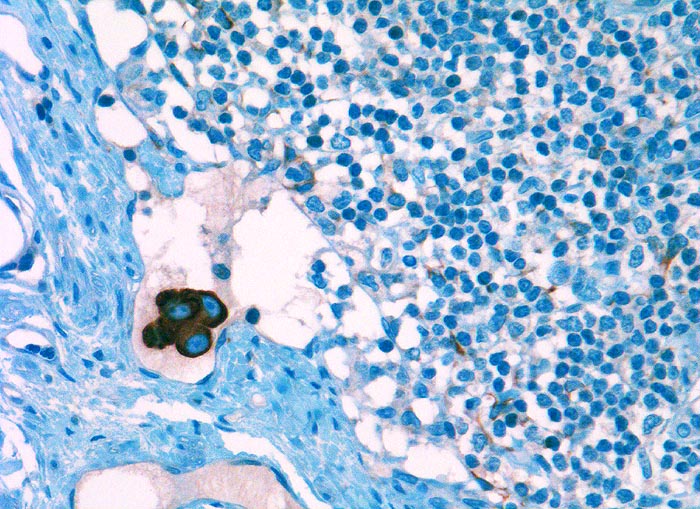

Tumor Einzelzellen in Lymphknotenrandsinus bei Mammakarzinom

Stark positiv angefärbte Tumorzellgruppe in einem Randsinus des Lymphknotens. Die Tumorzellkerne tragen grosse Nukleolen. Im Lymphknotengewebe unspezifische Anfärbung von Reticulumzellen mit sternförmigen Zytoplasmaausläufern.

Metastase im Sentinellymphknoten.

Immunhistochemie

CK22